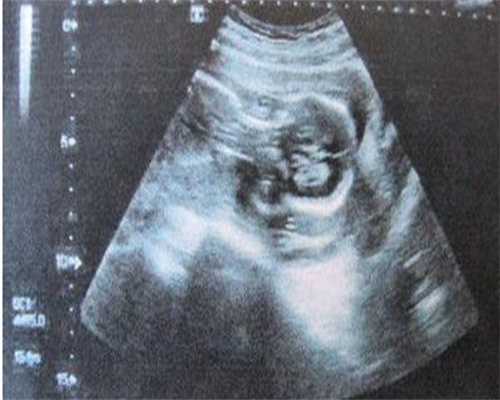

试管婴儿是供卵天子助孕的一种常见方式。在江苏地区,试管婴儿的流程通常是这样的:首先,女性进行促排卵治疗,以增加卵子的数量。然后,医生会在女性的卵巢中取出卵子,将其和男性的精子在实验室中进行受精。接着,医生会将受精卵培养几天,并选出最好的一个或两个受精卵,将其移植回女性子宫内。最后,女性需要进行一段时间的休息和观察,以确保胚胎成功着床。